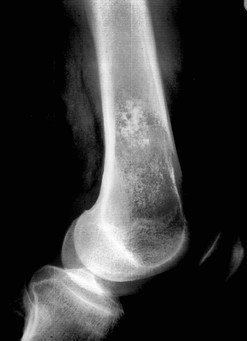

Tumeur osseuse visiblement maligne: quel est le diagnostic probable?

Lésion épiphysaire à matrice cartilagineuse (pop corn) d’allure maligne = Chondrosarcome de l’humérus